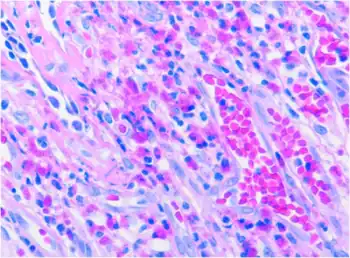

![]() | |

The dimeric IgA molecule. 1 H-chain, 2 L-chain, 3 J-chain, 4 secretory component | |